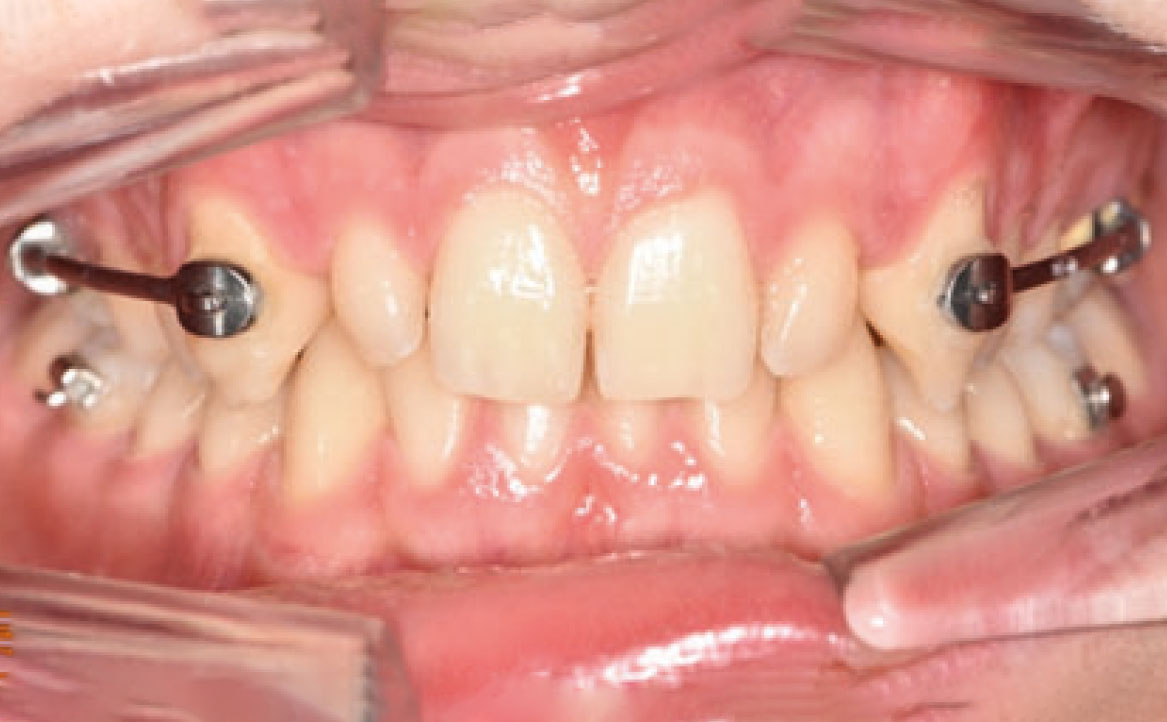

Il paziente si è presentato per la sua prima visita presso il reparto di Odontoiatria e Protesi Dentaria dell’Ospedale Vita-Salute San Raffaele diretto dal prof. E. F. Gherlone. All’esame obiettivo era evidente una malocclusione scheletrica e dentale di classe II associata a morso profondo e lieve affollamento anteriore superiore. In particolare, sono stati segnalati: rapporti occlusali di classe II, morso profondo, perdita di overjet, contrazione dell’arcata superiore e inferiore con leggero affollamento (fig. 1a-f). La richiesta del paziente era quella di migliorare l’estetica dei denti anteriori con allineatori invisibili di tipo Invisalign. Tuttavia, sia il paziente che il genitore sono stati informati che, per ragioni di efficacia e risoluzione del problema, era necessario agire anche a livello di funzionalità e risoluzione della malocclusione.

In primo luogo, sono stati prescritti entrambi gli esami radiografici ortodontici: OPT e teleradiografia latero-laterale del cranio (fig. 2a-b). Successivamente, in accordo con il genitore, è stata concordata una terapia ortodontica in due tempi. L’inizio della terapia è stato effettuato con Carriere Motion ed elastici di classe II, con l’obiettivo di migliorare la classe molare (fig. 2c-e).